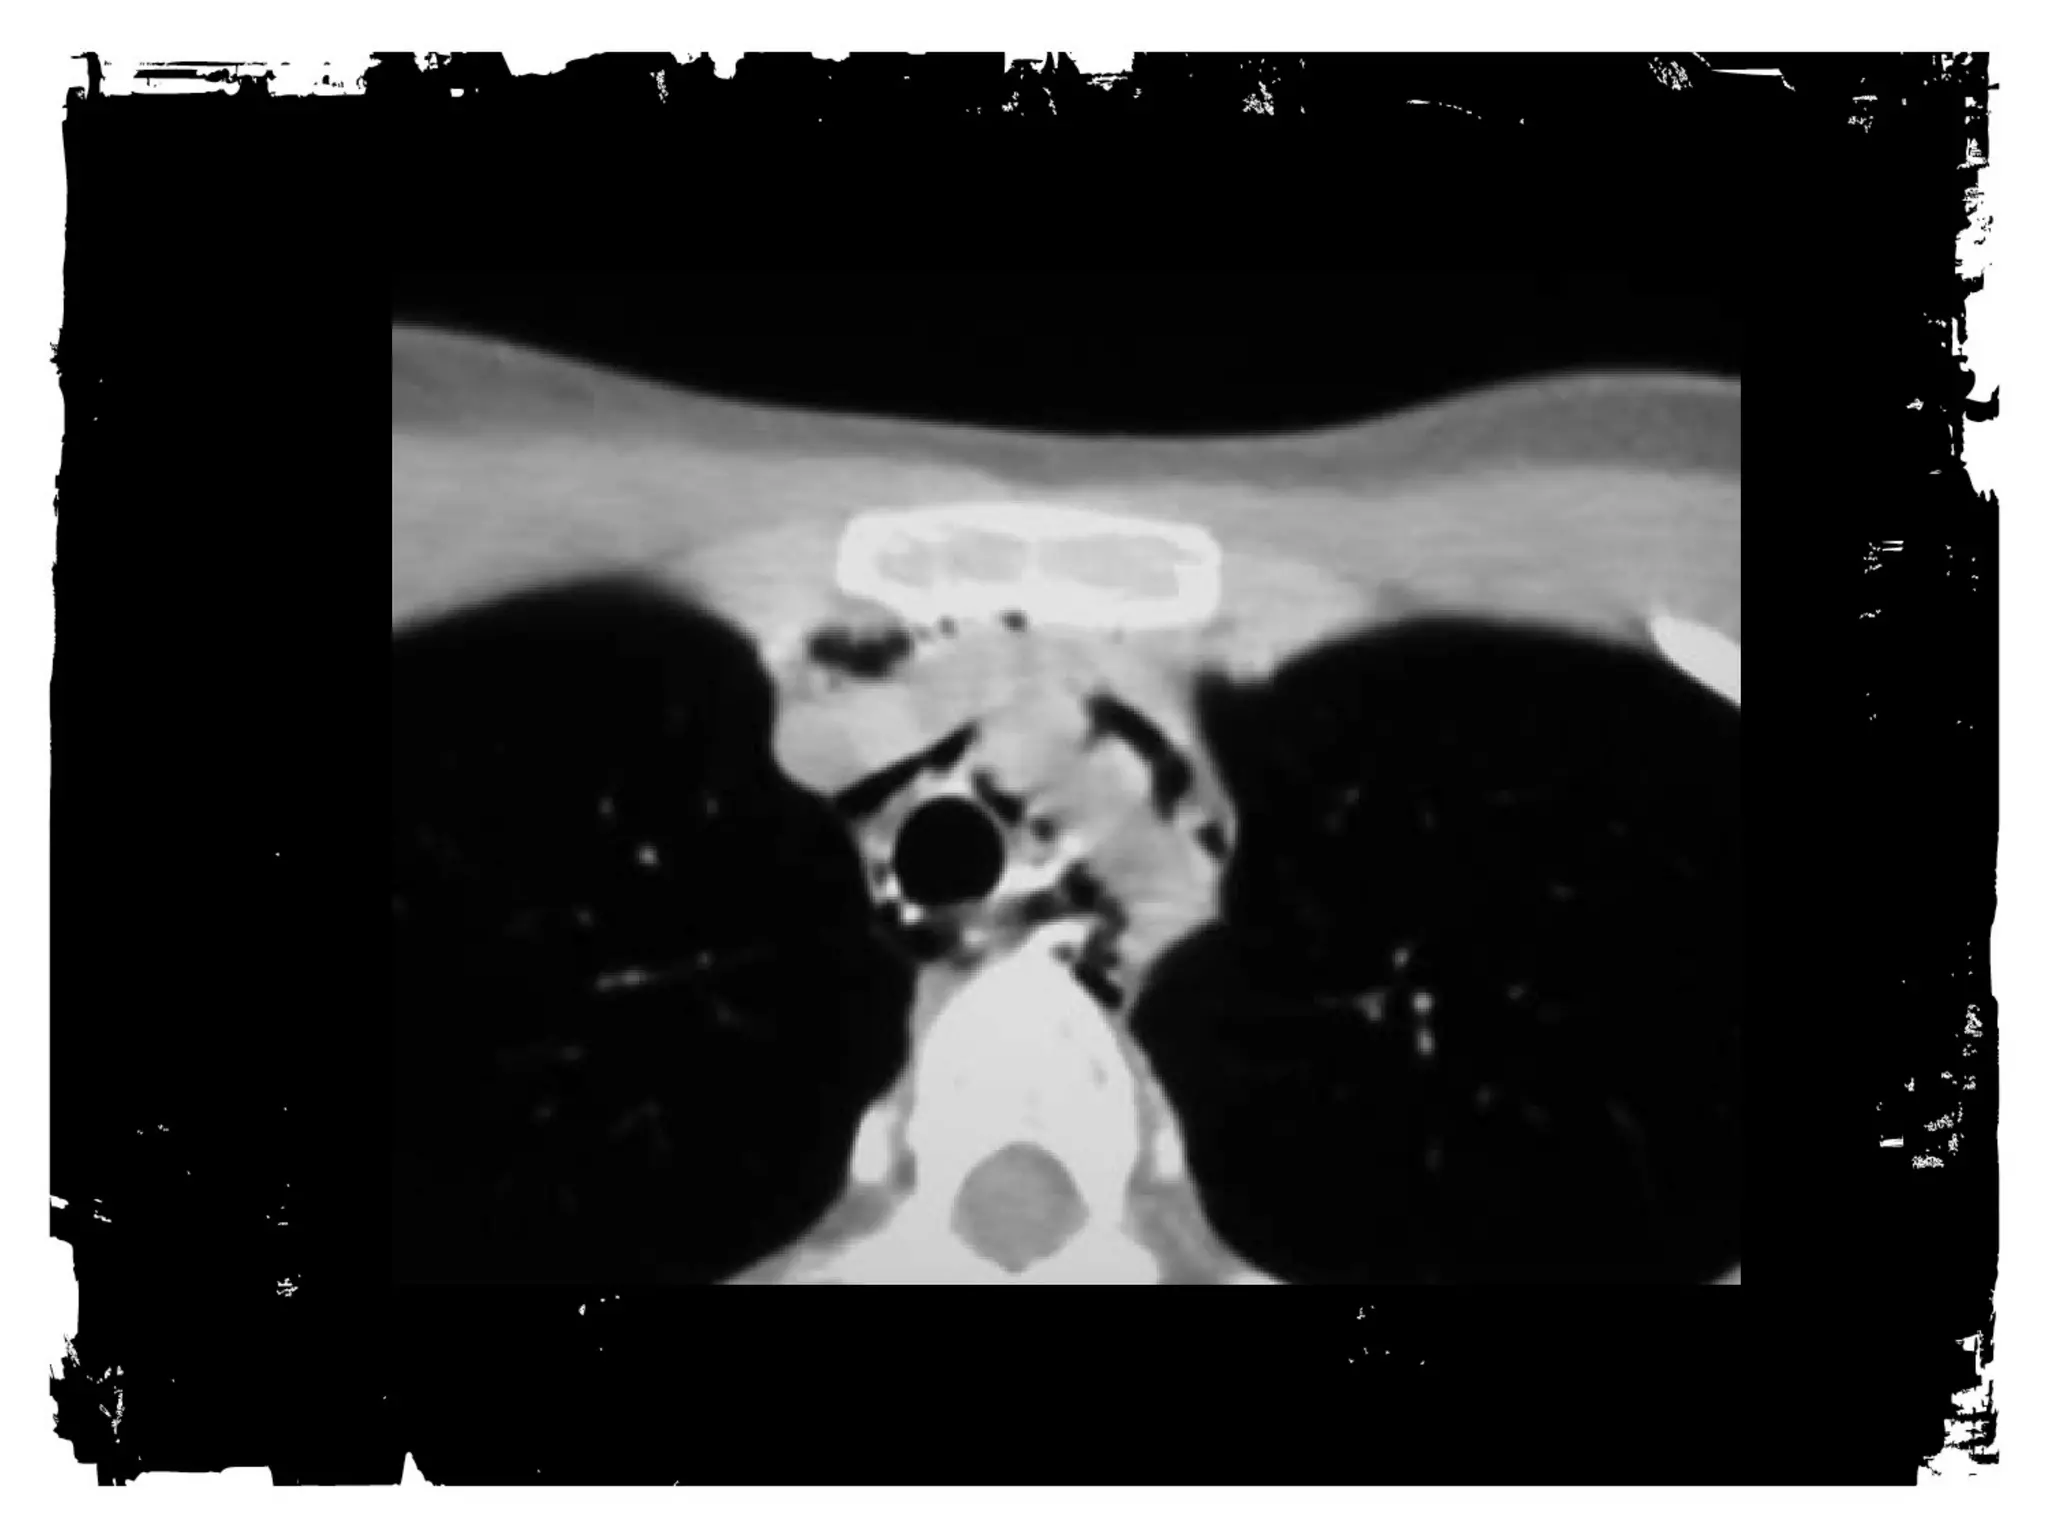

Sterno-Clavicular Dislocations

• Anterior: Not much of a

problem.

• Posterior: Less common; can

injure great vessels or trachea.

Sterno-clavicle dislocation: CT